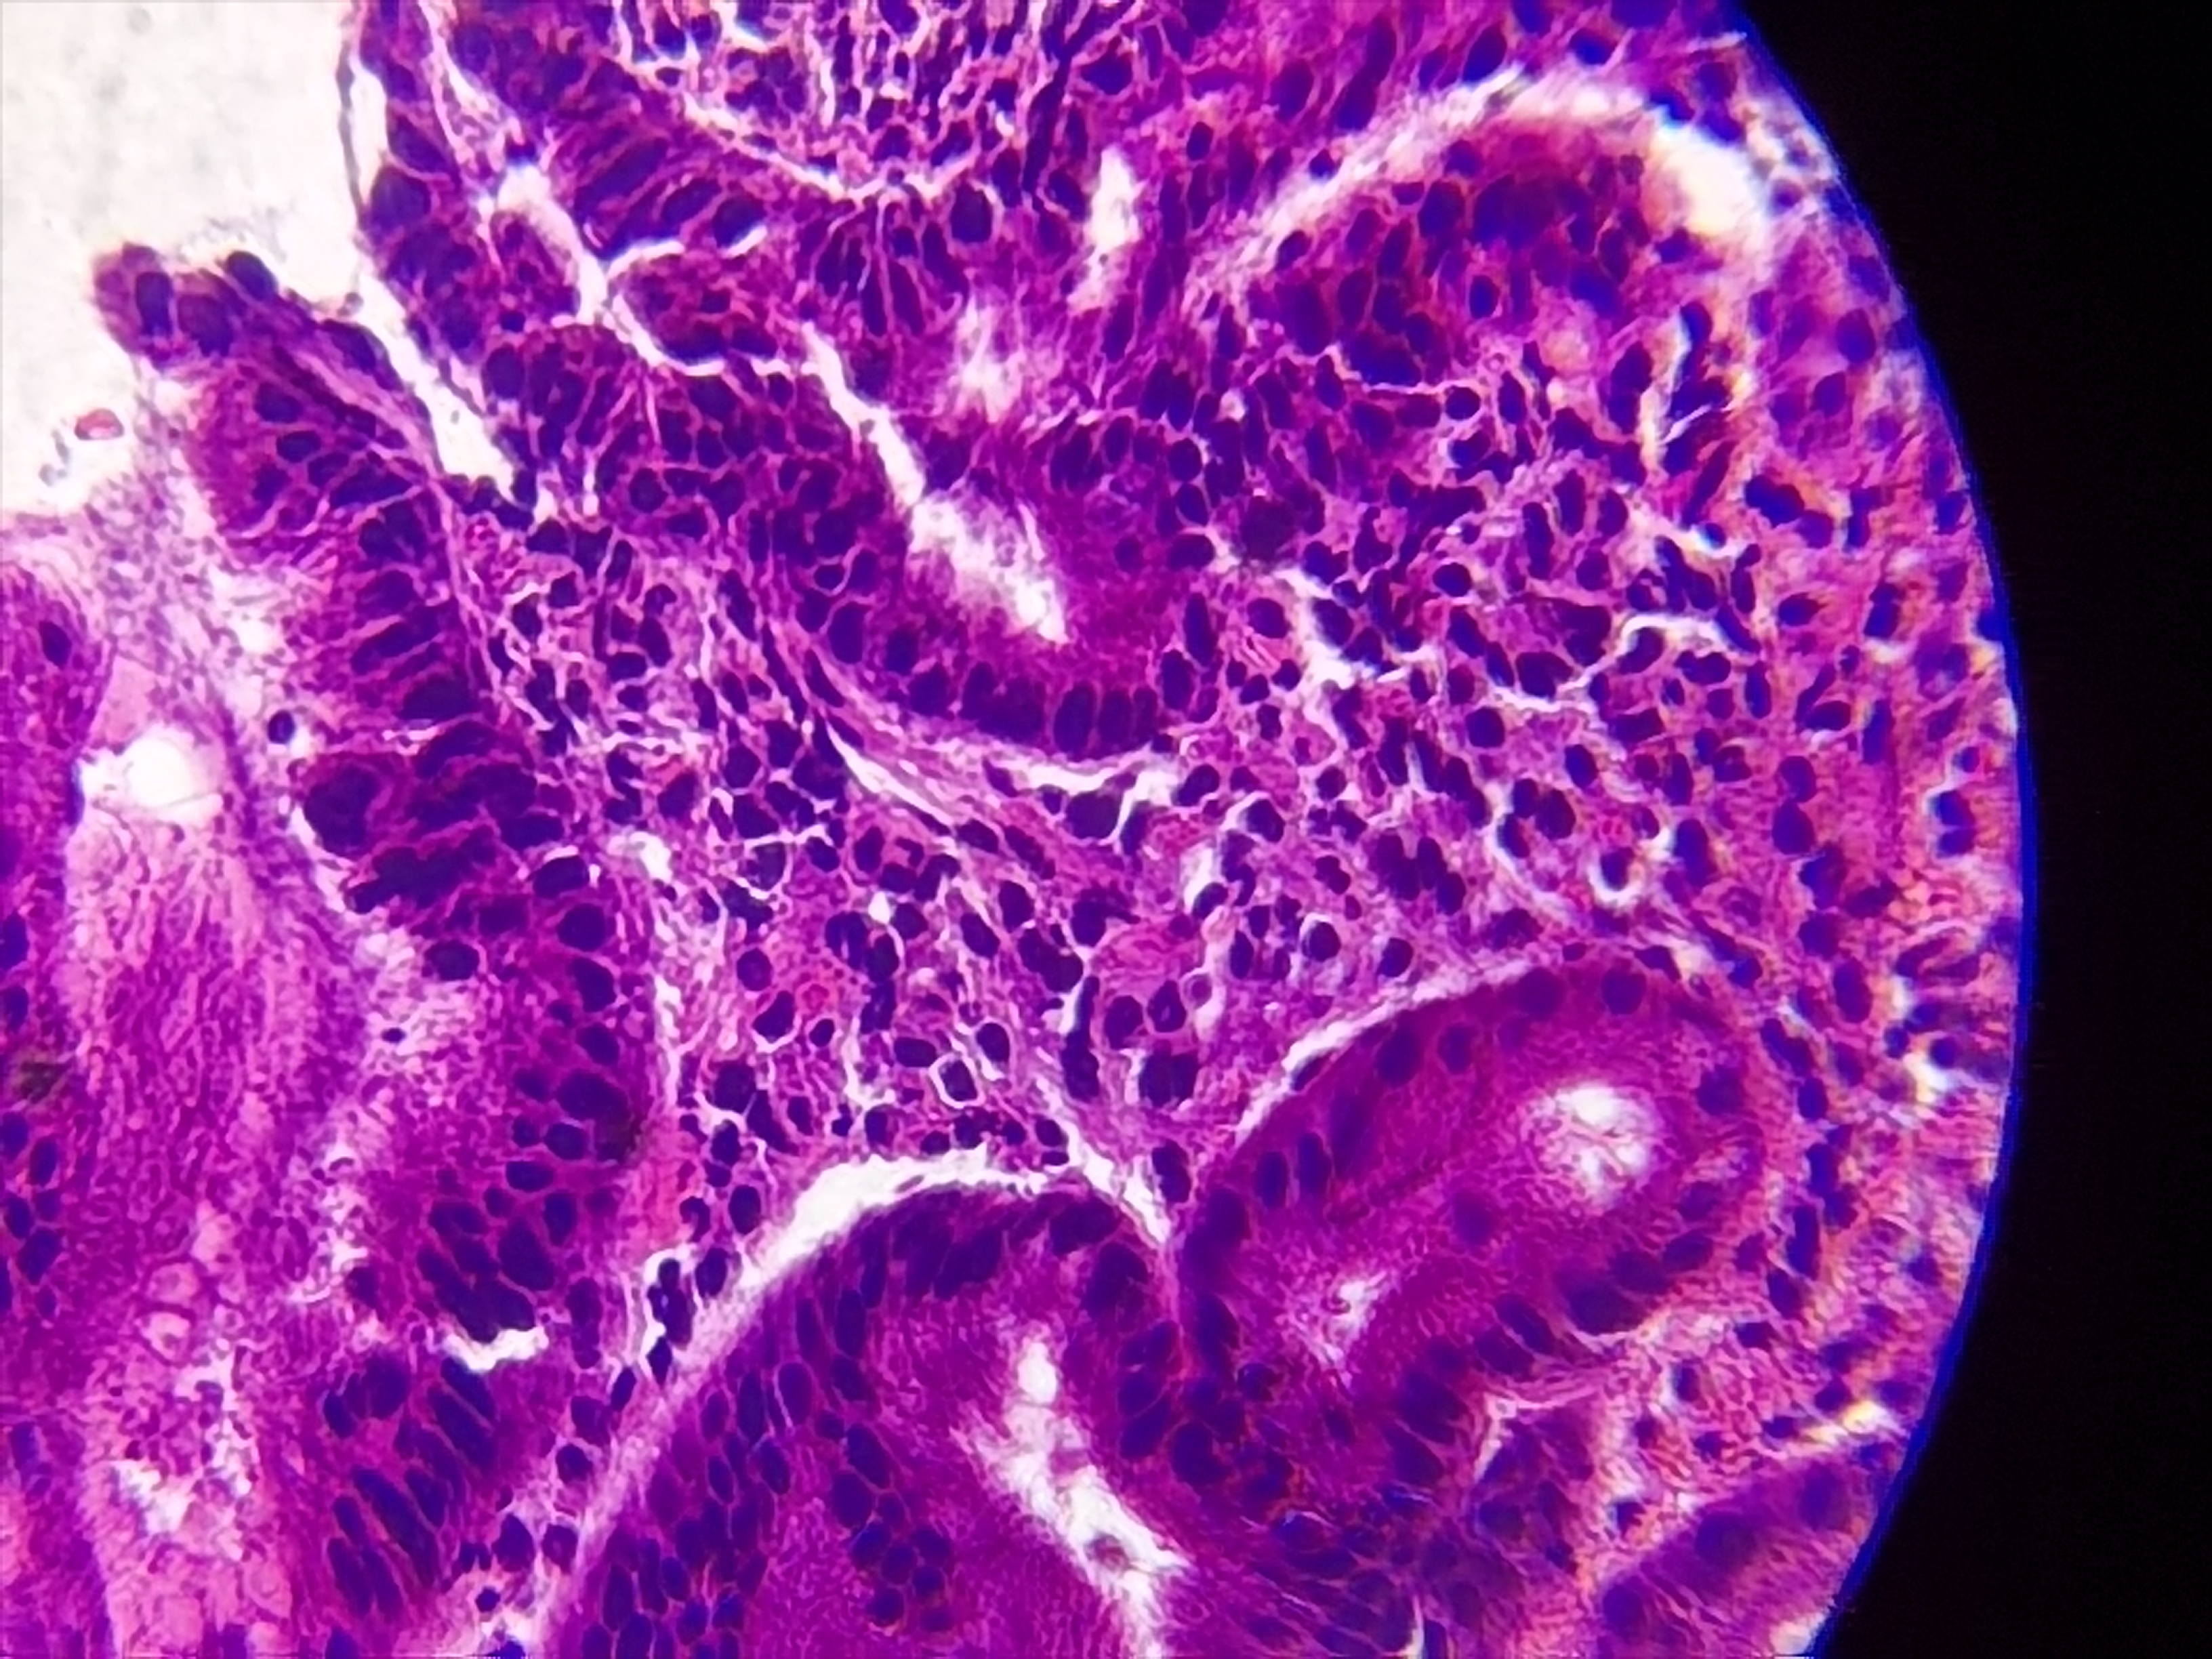

胃窦活检

胃窦部分粘膜表面血痂及少量渗血,多发白苔溃疡

胃窦粘膜活检

灰白色组织1块

良性的,片子质量不好!

考虑慢性活动性炎,图3靠右上方的那一个区域看上去有些模糊, 薄切一张重染再看看。